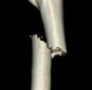

• 股骨干骨折不愈合再骨折合并内固定物断裂1例

股骨干骨折不愈合再骨折合并内固定物断裂1例

作者:山东中医药大学附属医院运动损伤骨科 李振宁 该病例是右股骨下1/3粉碎性骨折,用的是外侧钢板内固定。虽然再次外伤,但并非外伤所致的钢板断裂和再骨折。对此分析如下: